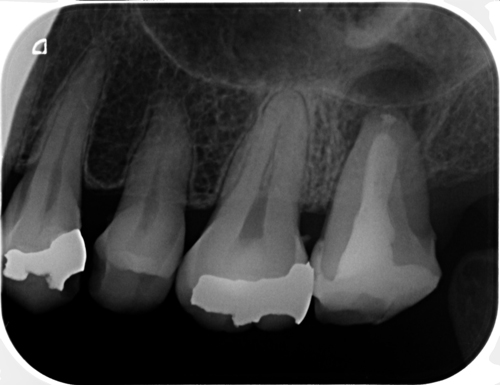

レントゲンでもずいぶん骨ができているように見えます。外科まで含んだ根管治療の治療費はトータルで20万円程度です。